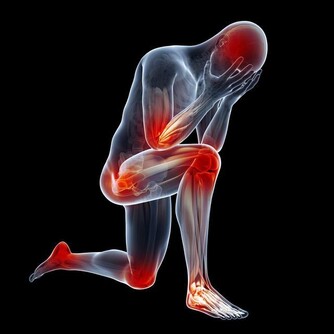

上班族每天久坐打電腦,腿部血液循環容易變差,

長期下來造成水腫,乍看之下變成小象腿,真是太冤枉!

久坐容易造成小腿水重,不妨適度按壓穴位,有助維持纖纖美腿

「白天坐辦公室,晚上坐沙發看電視」已經成了許多人的生活寫照,

一整天坐著的時間多達10幾個小時,又粗又腫的小象腿,就是這樣坐出來的。